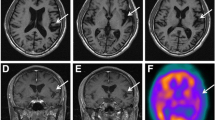

A 74-year-old woman was referred to our hospital and admitted for progressive speech and language difficulties. The patient was unable to recall the names of things or persons and was unable to communicate with others for about 1 year prior to admission, though she was able to shop and do housework without difficulty. She had no significant medical history; however, regarding her family history, her elder brother had developed word-finding difficulty with verbal paraphasia and right-hand limb-kinetic apraxia at the age of 62 years of age, and was diagnosed with CBS at 69 years of age. He had frontal lobe signs such as forced grasping, total aphasia, and right-limb kinetic apraxia; moreover, brain magnetic resonance imaging (MRI) demonstrated frontal and temporal lobar atrophy dominantly affecting the left side (Fig. 1a). The patient’s brother and parents had passed away; therefore, we could not obtain their detailed clinical information.

Brain MRI (axial T1-weighted images) of the patient’s brother (a) and the patient (b). a T1-weighted brain images of the patient’s brother at 4 years after disease onset. Atrophy was predominantly observed in the left hemisphere affecting the frontotemporal lobes. b T1-weighted brain images of the patient at 1 year after disease onset. Similar to her brother, atrophy was predominantly observed in the left hemisphere affecting the frontal and temporal lobes

Language function was assessed using the Western Aphasia Battery (WAB) Japanese edition once and SLTA (standard language test of aphasia) two times within 2 months. The scores of WAB subtests were as follows: spontaneous speech, 13 points; auditory verbal comprehension, 5.5 points; repetition, 0 points; naming, 0 points; reading, 4.3 points; writing, 2.2 points; praxis, 6.8 points; and construction, drawing, block design & calculation, 6.6 points. Raven’s score was 25/37 (average ± standard deviation: 26.9 ± 5.4). Aphasia quotient was 36.8. The results of SLTA were similar to those of WAB. Naming, writing, and repetition were impaired. However, auditory verbal comprehension and reading concerning words and short sentences were relatively preserved. Spatial perception and visual perception were also normal. Verbal comprehension via visual perception was approximately normal. Therefore, it is likely that auditory verbal comprehension was complemented by visual perception. Constructional dysfunction, limb-kinetic apraxia, ideational apraxia, and motor apraxia were not observed. Laboratory blood examinations did not reveal any particular abnormalities that could have caused cognitive dysfunction. Cell counts and protein concentrations in the patient’s cerebrospinal fluid were within normal ranges, and concentrations of tau protein (282 pg/mL) and phosphorylated tau protein (31.3 pg/mL or lower) were also normal. Brain MRI demonstrated cerebral atrophy dominantly affecting the left frontotemporal lobes (Fig. 1b).